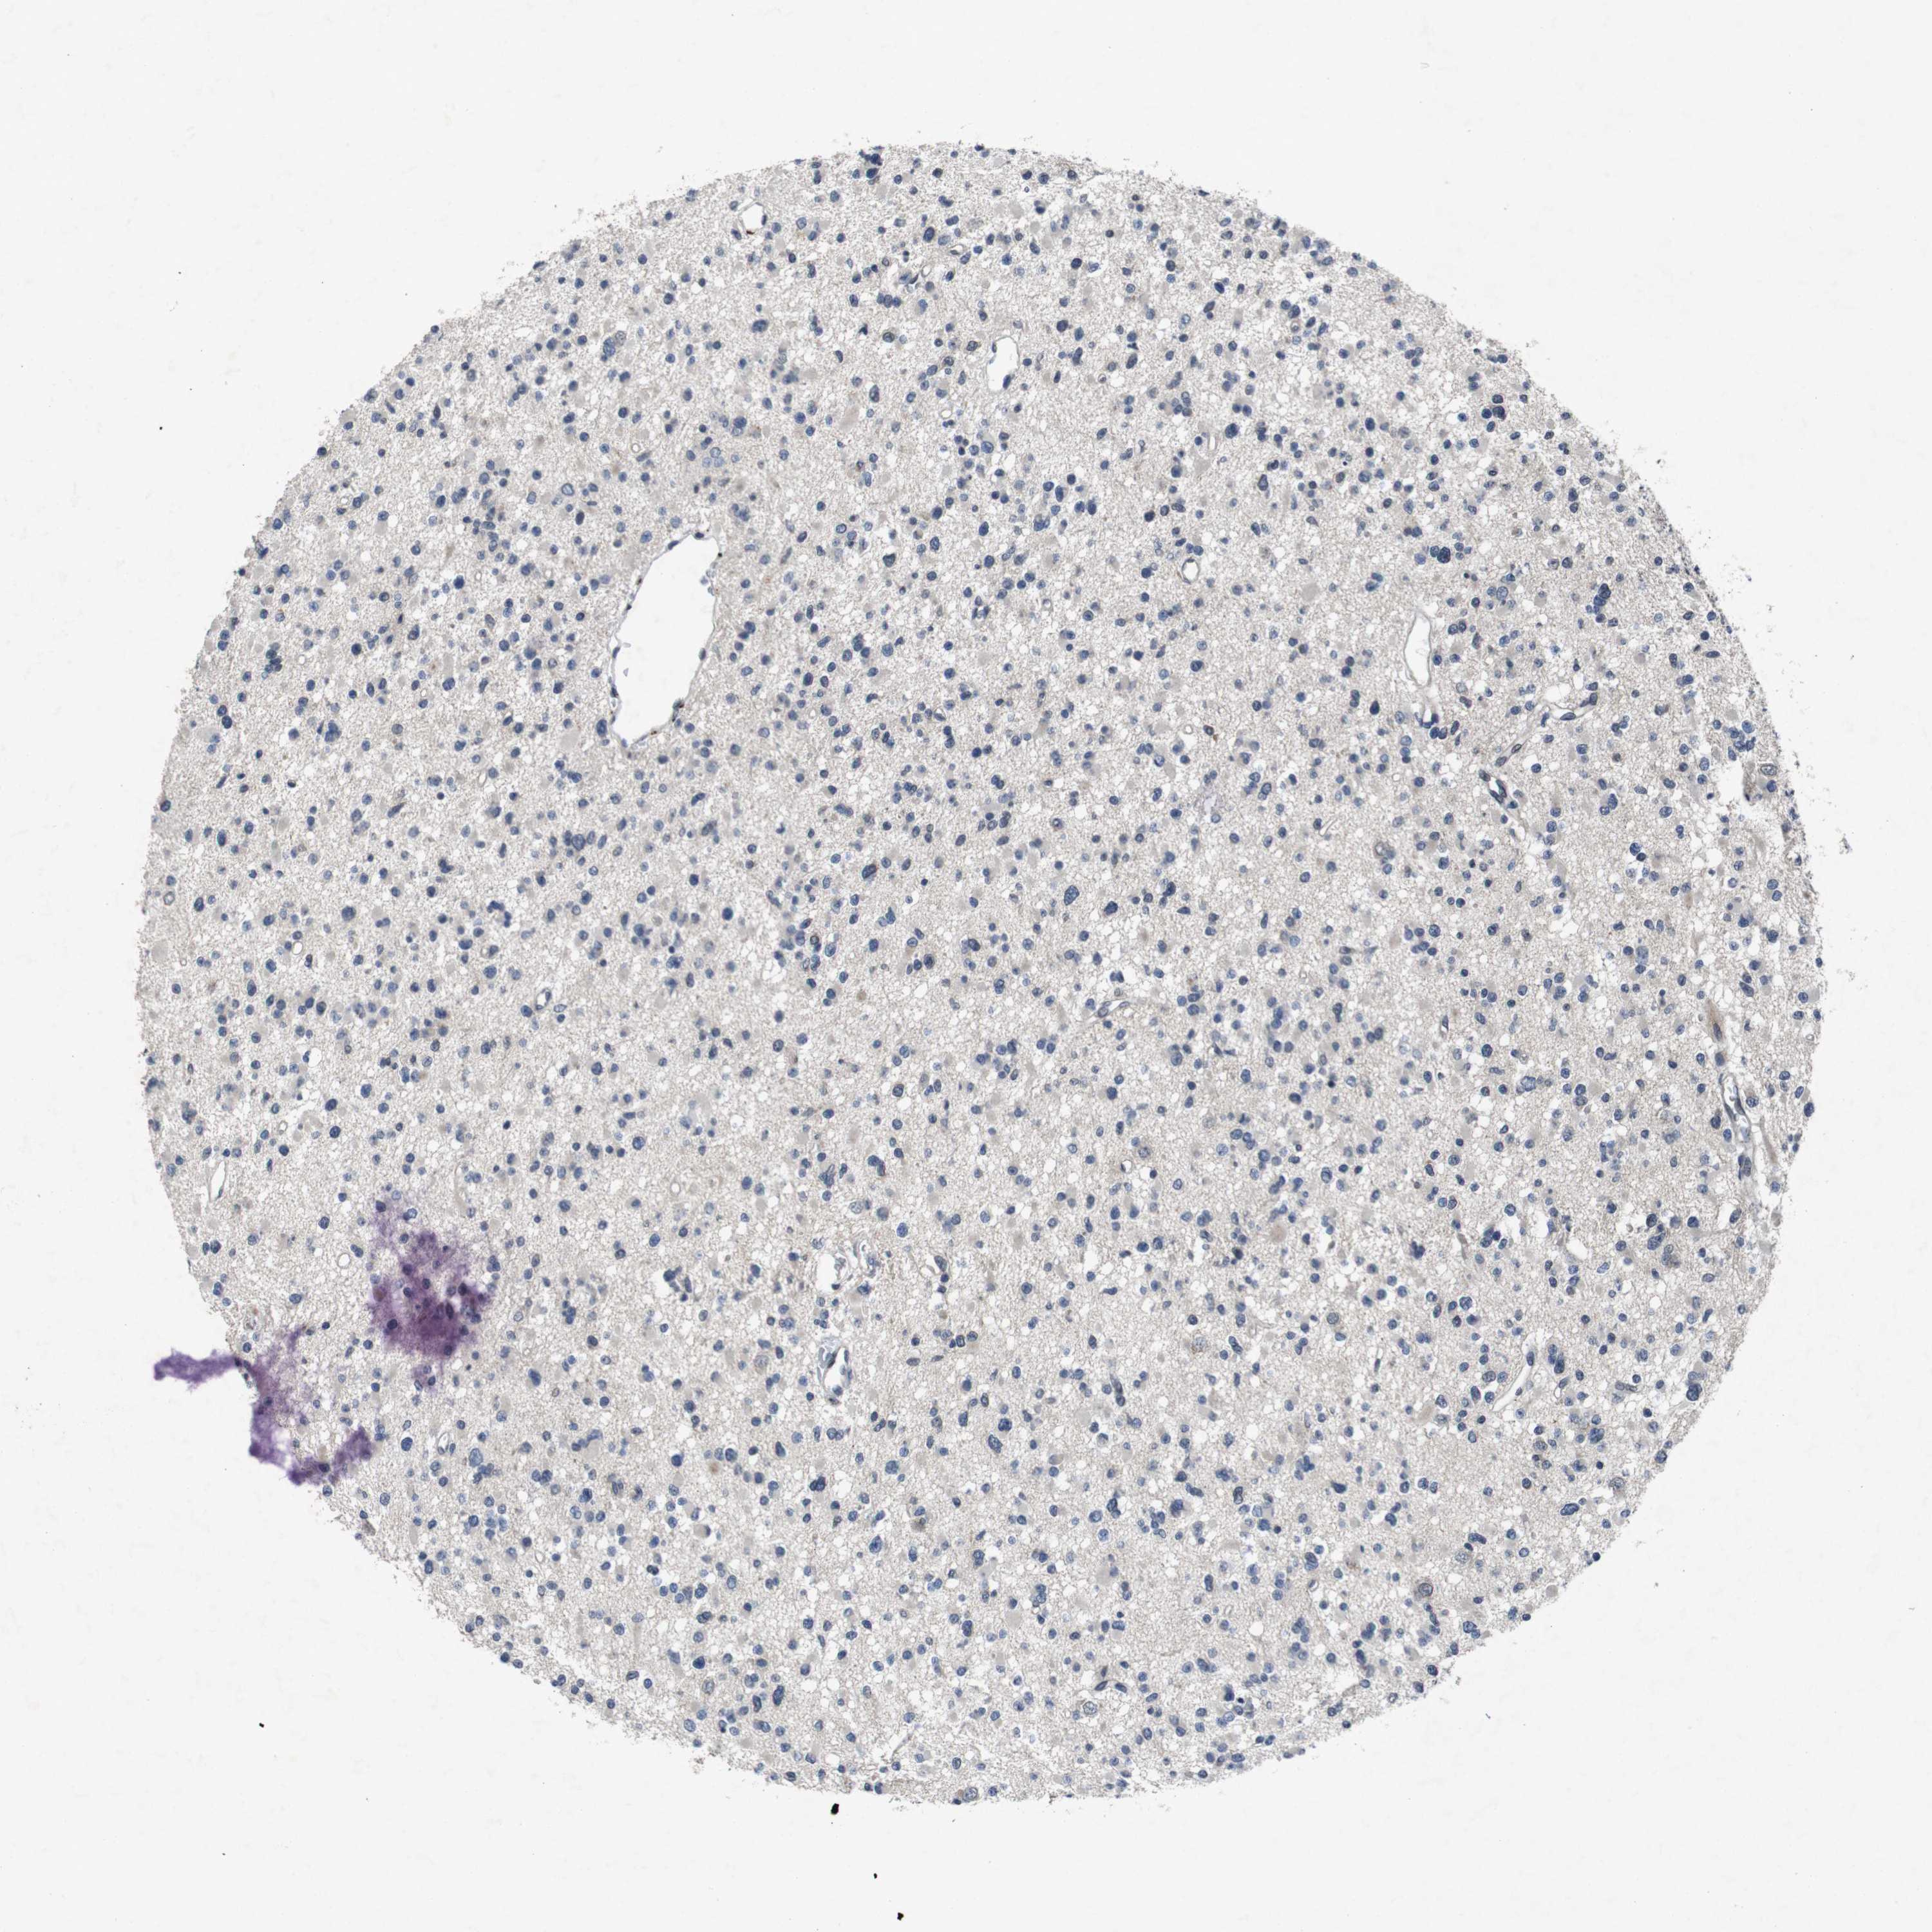

GLIOMA - Protein expressioni

A mouse-over function shows sample information and annotation data. Click on an image to view it in a full screen mode. Samples can be filtered based on level of antibody staining by selecting one or several of the following categories: high, medium, low and not detected. The assay and annotation is described here.

Note that samples used for immunohistochemistry by the Human Protein Atlas do not correspond to samples in the TCGA dataset.

Antibody stainingi

Antibody staining in the annotated cell types in the current human tissue is reported as not detected, low, medium, or high, based on conventional immunohistochemistry profiling in selected tissues. This score is based on the combination of the staining intensity and fraction of stained cells.

Each image is clickable and will lead to virtual microscopy that enables deeper exploration of all samples and also displays staining intensity scores, fraction scores and subcellular localization as well as patient and tissue information for each sample.

Antibody HPA026441

Antibody CAB013090

Staining

High

Medium

Low

Not detected

Intensity

Strong

Moderate

Weak

Negative

Quantity

>75%

75%-25%

<25%

None

Location

Nuclear

Cytoplasmic/membranous

Cytoplasmic/membranous,nuclear

Glioma, malignant, High grade

Glioma, malignant, Low grade